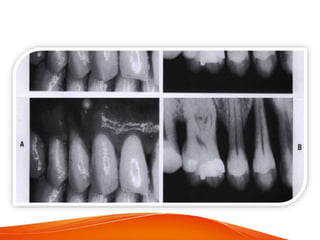

Intra oral radiographic survey

• Radiograph may sometimes reveal heavy calculus

deposits interproximally and even on the facial and